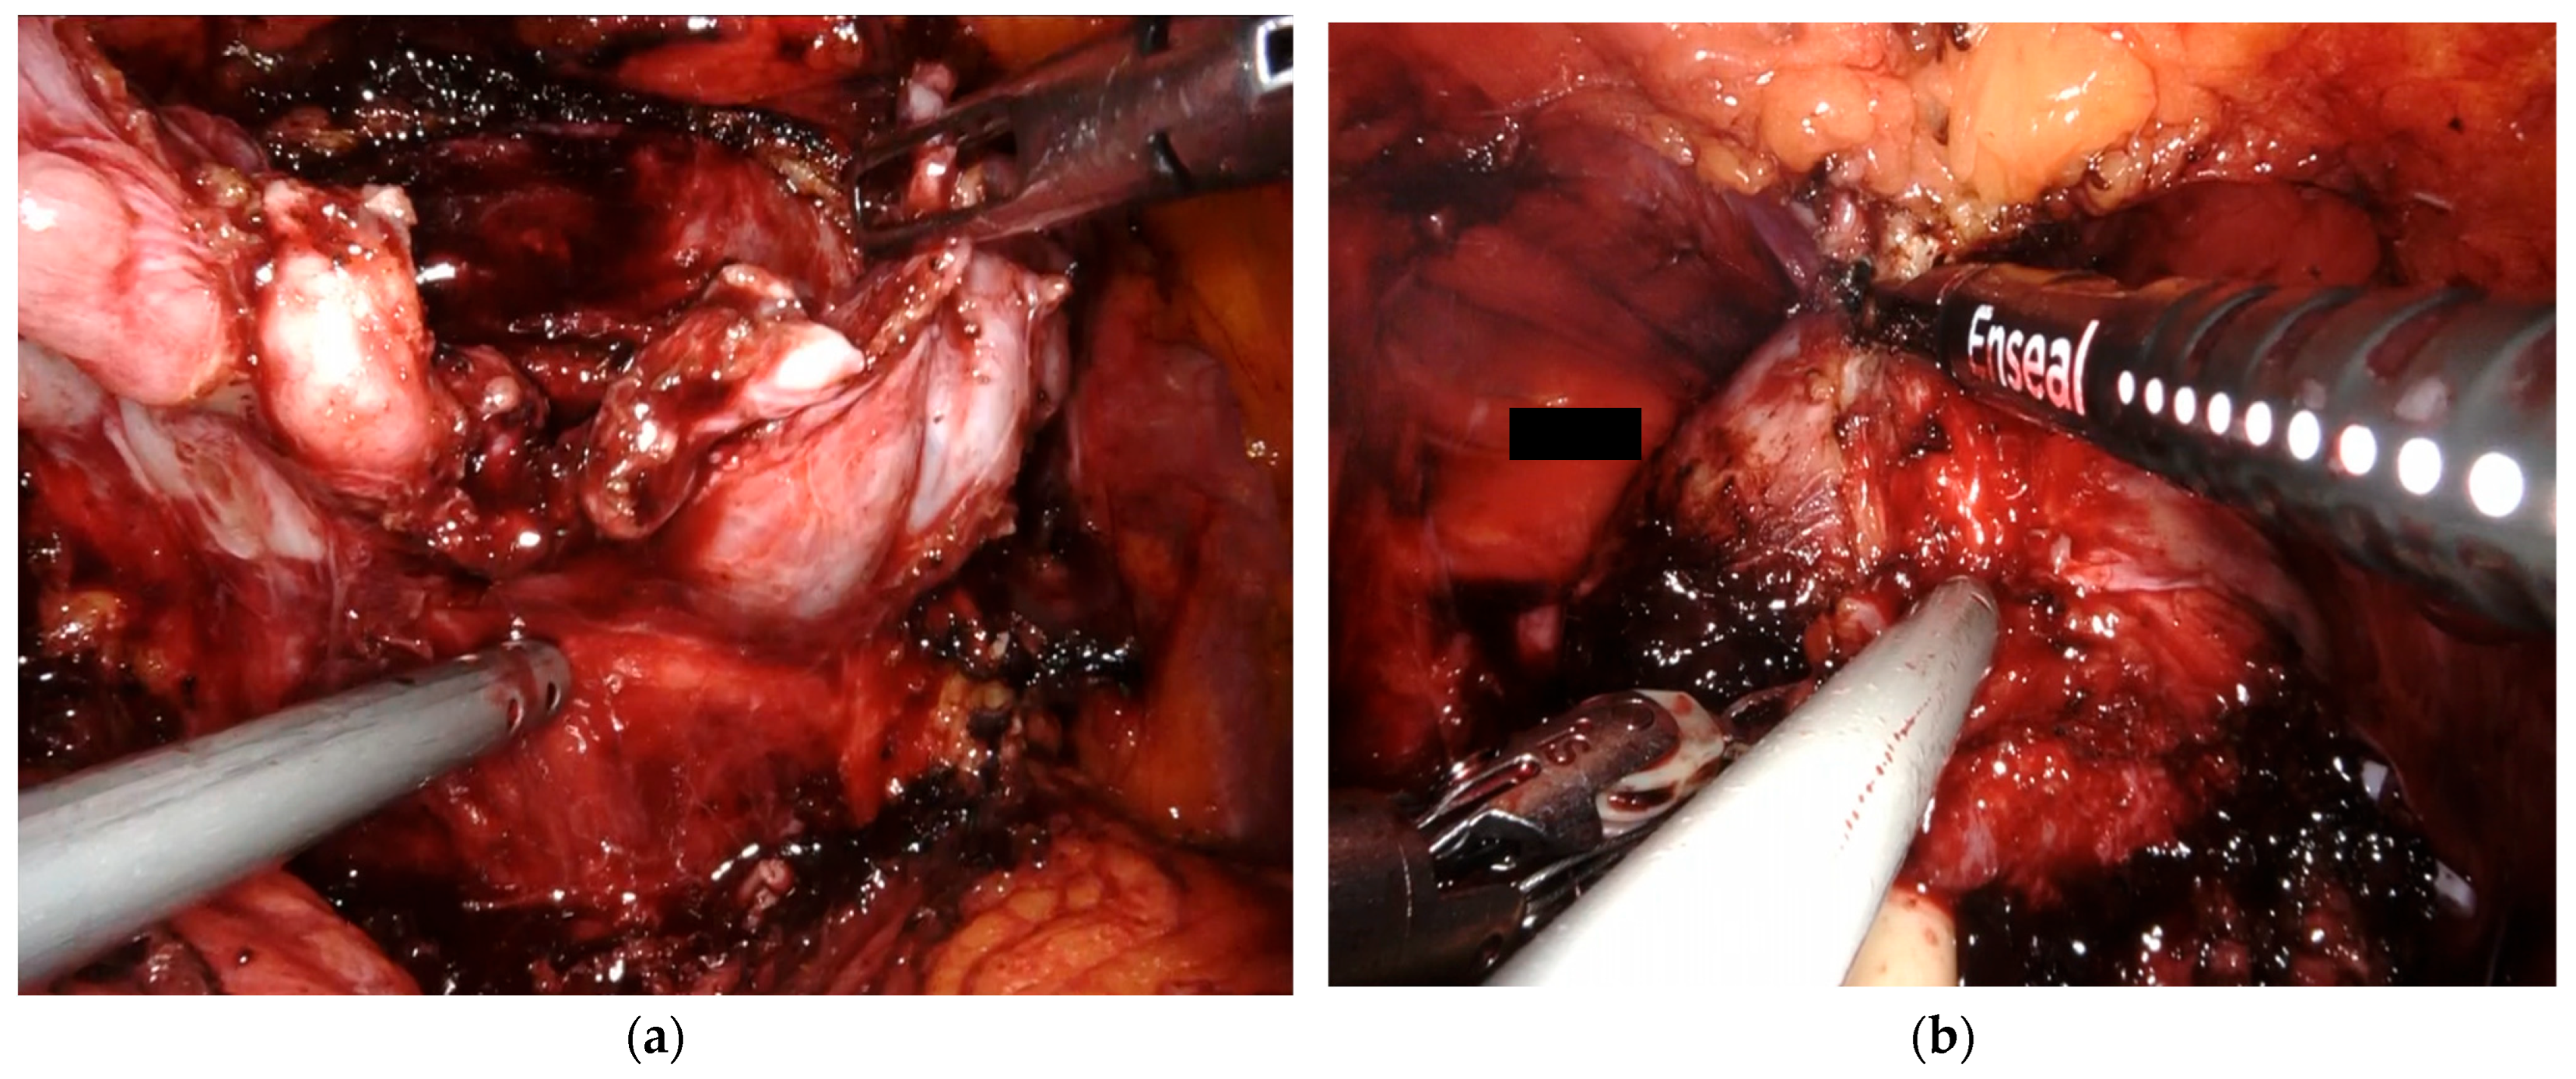

2.3. Surgical Procedure